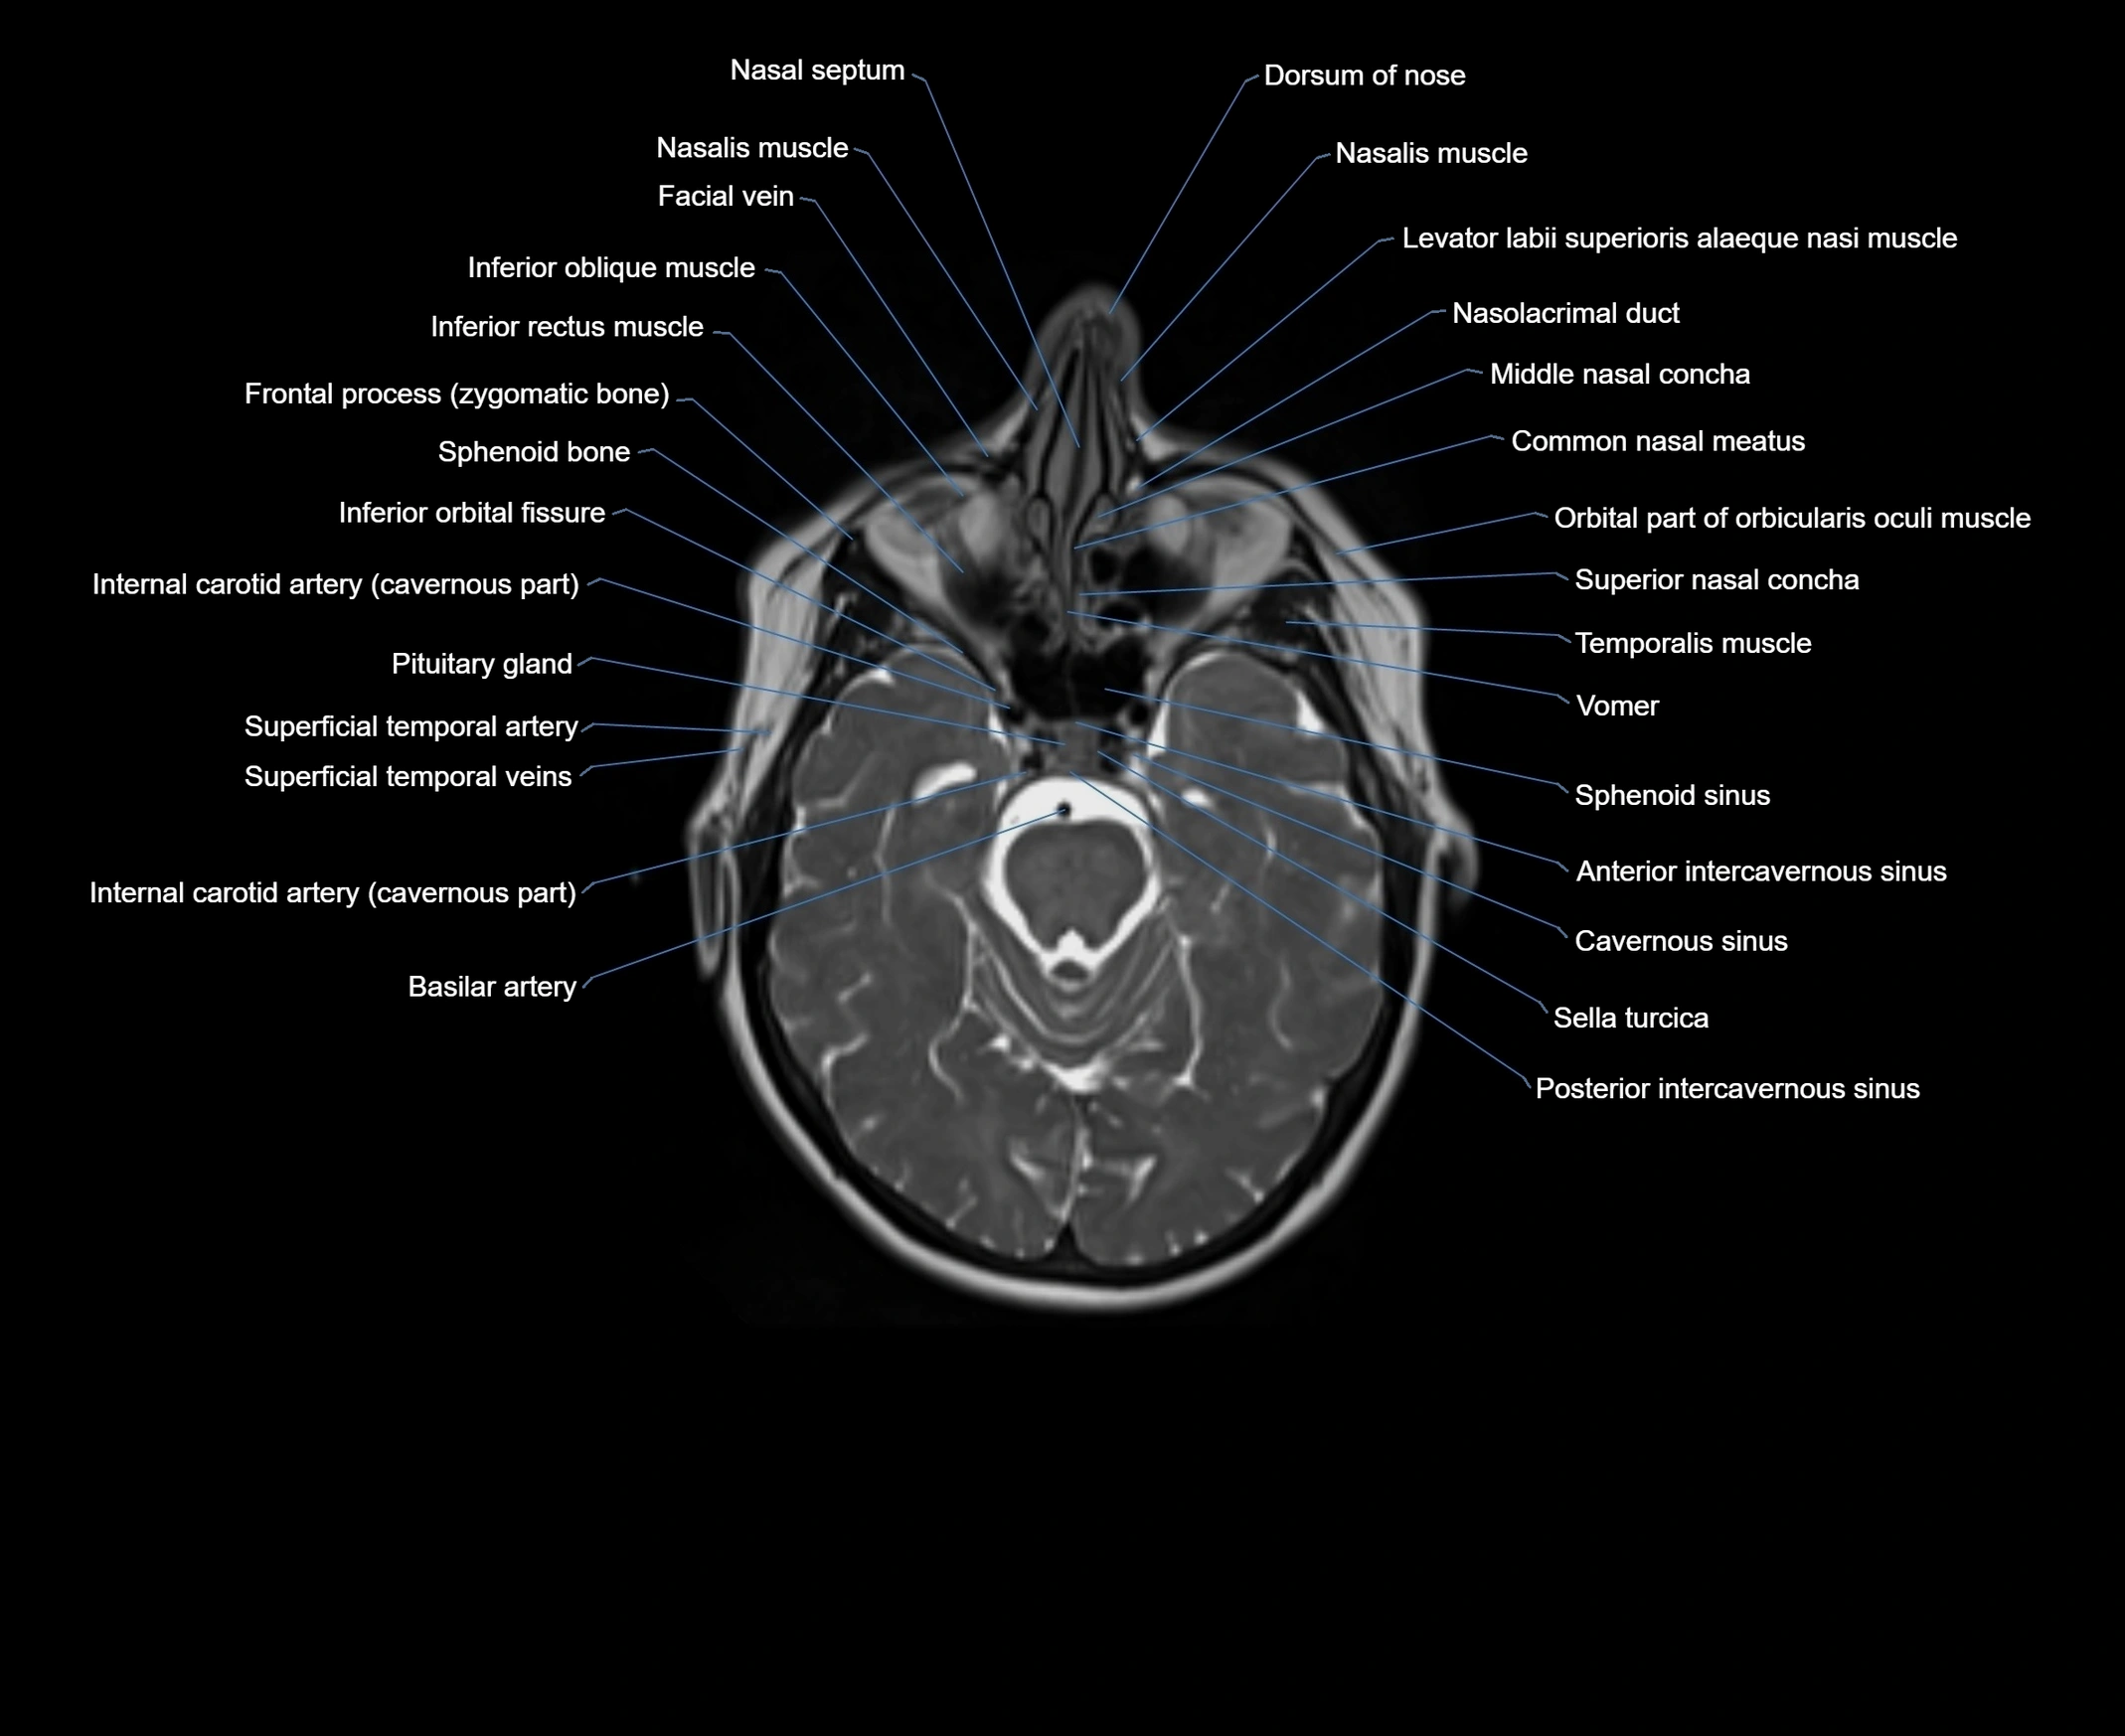

MRI images